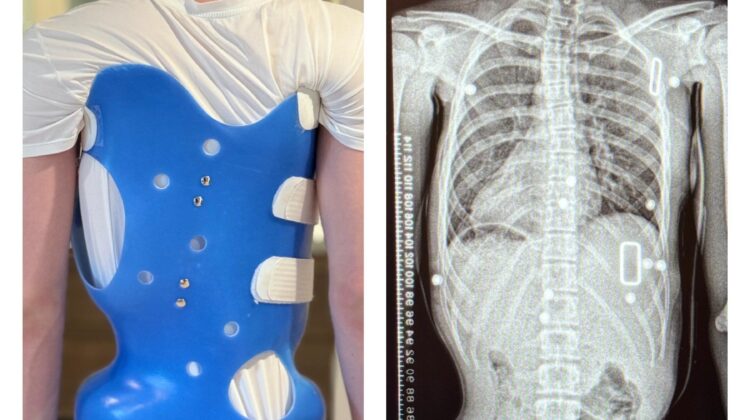

حزام اعوجاج العمود الفقري هو جهاز طبي يتم تصميمه خصيصًا لكل طفل، ويهدف إلى:

- دعم العمود الفقري

- تقليل الانحناء

- تحسين استقامة الجسم أثناء النمو

👉 من المهم أن تعرف أن الحزام لا يعالج الاعوجاج بشكل نهائي، لكنه يساعد على تقليل الانحناء خلال فترة النمو.

كيف يعمل حزام اعوجاج العمود الفقري؟

الحزام يعمل بطريقة ذكية تعتمد على:

- توجيه نمو العمود الفقري

- تقليل الضغط على المناطق المنحنية

- دعم الوضعية الصحيحة للجسم

التطور الكبير في تصميم الأحزمة الطبية جعل علاج اعوجاج العمود الفقري عند المراهقين أكثر نجاحًا وأقل إزعاجًا. باستخدام تقنيات التصوير الثلاثي الأبعاد والمحاكاة الرقمية، أصبح الحزام أكثر خفة وراحة، ويعطي نتائج أفضل في تصحيح الانحناء والتواء العمود الفقري.

الرسالة للأهل: إذا كان طفلك بحاجة إلى حزام طبي، اسأل الطبيب دائمًا عن التصميم الحديث المصنوع بتقنية ثلاثية الأبعاد، لأنه قد يكون الفرق بين علاج ناجح وفعّال، وبين نتائج محدودة.